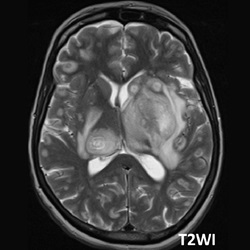

#AJNRcc >> October 30, 2025 >> What is the diagnosis for this 46-year-old man with seizures for more than 2 months. Submit your answer at https://t.co/FSqHPsLbMs.